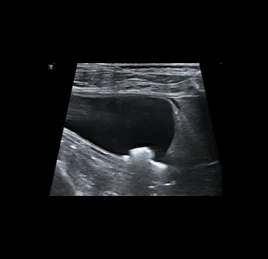

초음파 검사는 고주파 음파를 이용해 장기와 조직의 실시간 움직임을 영상으로 확인하는 비침습적 진단법입니다.

장기의 구조뿐 아니라 혈류, 운동성, 기능 변화까지 평가할 수 있어, 다양한 질환의 조기 발견과 모니터링에 효과적입니다.

📍초음파 진단 케이스

• 담낭 점액종